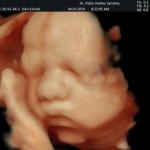

Los objetivos más importantes de esta ecografía son la evaluación de:

- La vitalidad y el bienestar fetal (Doppler).

- Crecimiento fetal.

- Las estructuras anatómicas fetales: diagnóstico de Malformaciones Estructurales de aparición tardía (displasias esqueléticas, alteraciones cardiacas pequeñas, alteraciones la vía urinaria y obstrucciones intestinales.

- Rastreo de alteraciones cromosómicas (sensibilidad del 55% aprox.).

- El escenario Gravídico: Placenta, liquido y Anexos.

- El Doppler de las arterias uterinas maternas y determinación de riesgo para pre eclampsia severa.